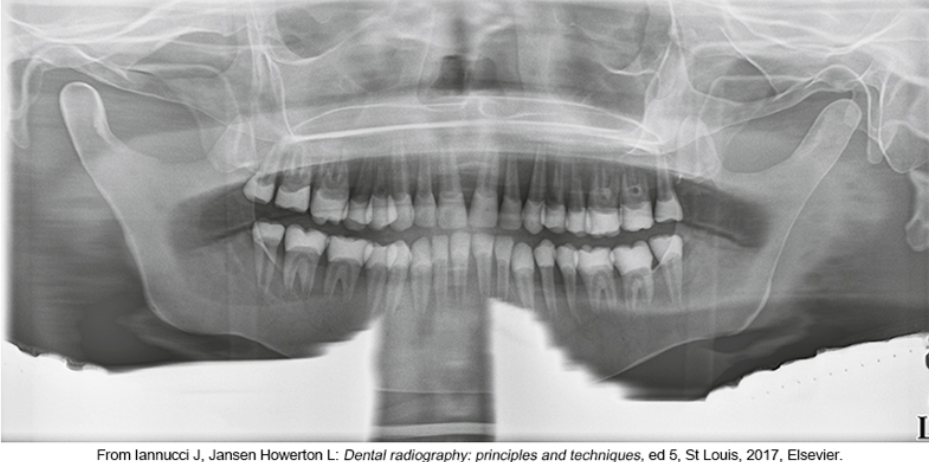

whats the problem

lips arent closed and tongue isnt on palate